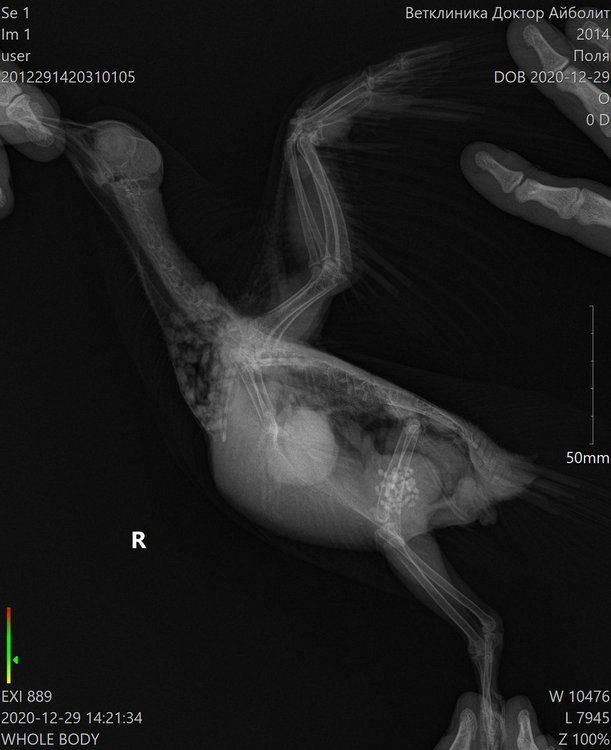

Lia V Опубликовано 30 декабря, 2020 Автор #25 Опубликовано 30 декабря, 2020 Добрый вечер, как обещала, рассказываю о результатах похода к хирургу. Вчера сделали операцию моему красавцу. Он, мягко говоря был сильно удивлен, сказал, что ранее такого не встречал. Приложу фото, которое он сделал во время операции. Этих шишек было 2, размеры и скорость роста шокируют (((((((((( одну хорошо видно на рентгене, вторая была на крыле (на плече, она была меньше, скрыта в перьях и не так заметна, на фото именно она). Природа этих наростов не ясна((((( Гистология будет готова только через 21 день. Назначили пить амоксиклав, флуконазол, гепатовет, кальция глюконат, транексам, ветом. Завтра записалась на контрольный повторный прием к орнитологу. Попрошу ее дотошно его с ног до ушей осмотреть (у меня это получается плохо, он вертится, я все время боюсь, что швы разойдутся и не рискую его сильно крутить. У врача, естественно, это получается ловко и умело). По цене операция + 2 проекции рентгенографии и гистология вышли в 7.300 руб. Сидит мой Поля с собранным крылом, в воротнике, летать не пускаю, гуляет только по клетке. Скучно ему. От избытка энергии чистится как дурной (ему больше реально и делать нечего), воротник спасает лишь частично, я все переживаю как бы не расковырял раны. Честно говоря, у меня паника и ощущение полой неопределенности. Спасибо врачам огромное, но ситуация все равно пока не ясная совершенно. Встречалась ли Вам такая ситуация??? Что это может быть???

Zosia Опубликовано 30 декабря, 2020 #26 Опубликовано 30 декабря, 2020 Меланома или меланоцитома. Встречались, конечно... Кроме всего прочего у птицы гипертрофия сердечной мышцы, дилатированное сердце. Есть так же некие объекты по верхней границы печени (в ВД проекции) и справа (для смотрящего на снимок- слева) https://public.fotki.com/Shemlik/cancer/operacia001.html https://public.fotki.com/Shemlik/cancer/55.html https://public.fotki.com/Shemlik/cancer/59.html#media https://public.fotki.com/Shemlik/cancer/05-09-20-002.html https://public.fotki.com/Shemlik/cancer/05-09-20-001.html#media